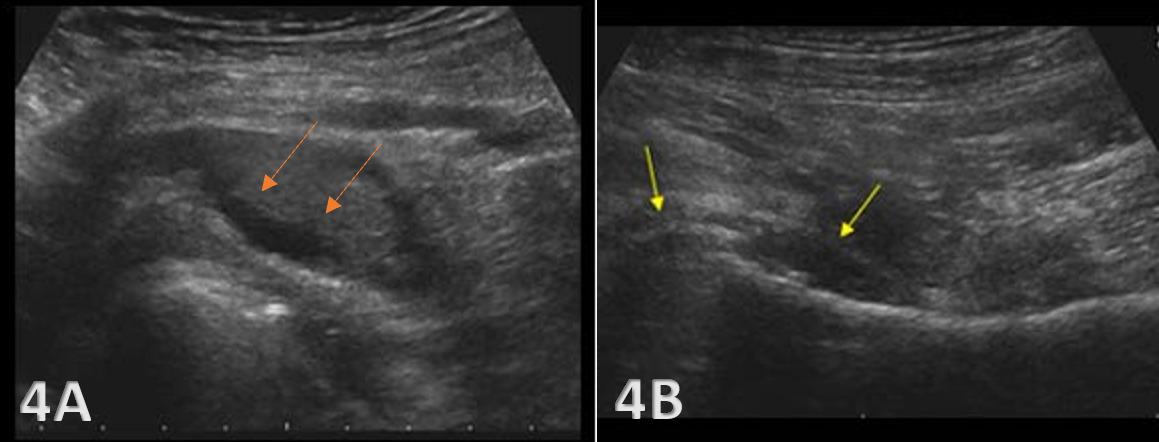

26. Ekstrand J, Lundqvist D, Davison M, D’Hooghe M, Pensgaard AM. Communication quality between the medical team and the head coach/manager is associated with injury burden and player availability in elite football clubs. Br J Sports Med 2019;53(5):304-308. doi:10.1136/ bjsports-2018-099411

27. Little C, Lavender AP, Starcevich C, et al. Understanding fear after an anterior cruciate ligament injury: a qualitative thematic analysis using the common-sense model. Int J Environ Res Public Health 2023;20(4). doi:10.3390/ijerph20042920

Solie B, Carlson M,

C,

Oh, My Quad: A Clinical Commentary And Evidence-Based Framework for the Rehabilitation of Quadriceps Size and Strength after Anterior Cruciate Ligament Reconstruction. IJSPT. 2024;19(12):1600-1628. doi:10.26603/001c.126191

Braidy

Solie1 a , Mitchell Carlson2 , Christopher Doney1 , Michael

Kiely

3 , Robert LaPrade4

1 Physical Therapy, Twin Cities Orthopedics, 2 Bioengineering Lab, Twin Cities Orthopedics , 3 Sports Science, Twin Cities Orthopedics, 4 Orthopedic Surgery, Twin Cities Orthopedics